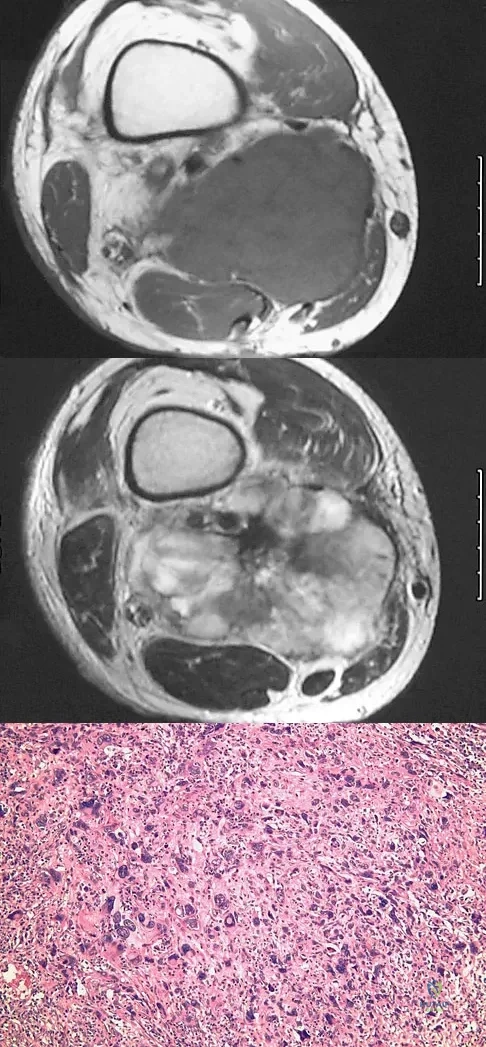

Question 49

An otherwise healthy 75-year-old man has a painful mass in the popliteal fossa of his right knee. A lateral radiograph of the knee, a CT scan of the distal femur, and a histopathologic specimen are shown in Figures 13a through 13c. Management should consist of

Explanation